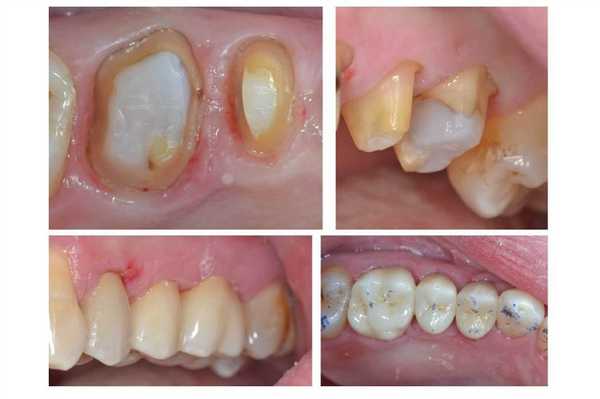

Фото 3. Большие кариозные дефекты зубов UL5 и UL6. Перед проведением эндодонтических вмешательств были выполнены реставрации с применением специальных матричных систем. Культи зубов восстанавливались при помощи стекловолоконных штифтов и композита. После поднятия уровня поддесневого края дефекта и препарирования на зубы фиксировали циркониевые коронки.

Когда следует проводить DME для зубов, требующих эндодонтического лечения?

Перед проведением эндодонтического лечения важно оценить, можно ли вообще восстановить зуб. Для этого первоначально нужно удалить весь кариес и прежние реставрации, а также установить, можно ли обеспечить выполнение новых герметичных реставраций. В процессе врач может провести DME и выполнить преэндодонтическую подготовку зуба. После лечения корневых каналов на край композитной пломбы может быть установлена непрямая реставрация. При выполнении преэндодонтического восстановления не всегда можно сформировать адекватный контакт (фото 4). Но на данном этапе это не так и важно, поскольку контактный пункт может быть восстановлен за счет окончательной реставрации. Куда более важно - удалить все нависающие края материала, поскольку они в последствии могут вызвать развитие пародонтальных проблем. Процедуру удаления излишков можно провести или скальпелем, или очень тонким бором. Если же зуб планируется восстановить лишь за счет композитной реставрации, то контактный пункт можно сформировать в конце, просто заново восстановив стенку, но уже с уровня, сформированного в ходе DME.

Фото 4. Лечение корневого канала, установка стекловолоконного штифта и восстановление культи зуба LL5. Глубокий край дефекта был восстановлен посредством DME. Контактный пункт будет откорректирован на финишном этапе реставрации.